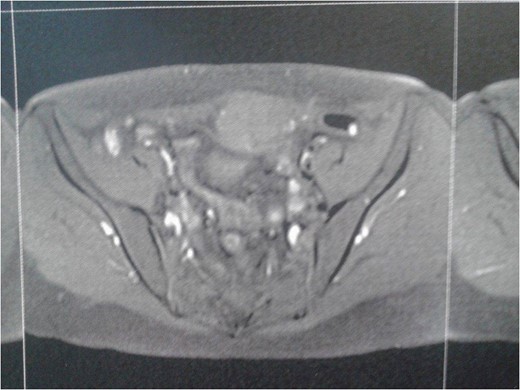

Complete blood laboratory tests, including tumor markers, showed values within normal limits. An abdominal computerized tomography and magnetic resonance imaging were performed; the latest revealed that the mass presented dimensions of 6.7 × 4.9 × 3.5 cm3, was located on the left rectus abdominis muscle, whereas no further intra-abdominal pathologic conditions were found (Figs 1 and 2). After adequate information and written consent, the patient was submitted to surgical excision of the mass.